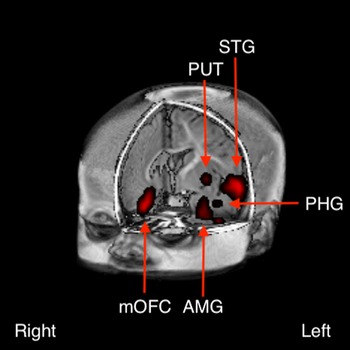

Following FDR correction for multiple comparisons (Benjamini & Yekutieli, Reference Benjamini and Yekutieli2001), between-group differences were detected in several clusters at p < 0.005 (Fig. 1). These included left dominant activations in the anterior temporal pole [predominantly superior temporal gyrus (STG)], striatum, amygdala/parahippocampal gyrus and putamen, and right dominant activations in the orbitofrontal cortex, and inferior frontal gyrus (IFG).

Fig. 1. Between-group difference in brain activation to the contrast of emotional positive (laughter) v. negative (crying) sounds between infants born to depressed v. non-depressed mothers (p < 0.005). These included left dominant activations in the anterior temporal pole [predominantly in the superior temporal gyrus (STG)], amygdala (AMB), parahippocampal gyrus (PHG) and putamen (PUT), and right dominant activations in the medial orbitofrontal cortex (mOFC).

Our findings indicate that infants exposed to PMD exhibit differences in activation within a frontal-limbic neural network. More specifically, we report, for the first time, that infants born to mothers with PMD exhibit greater activation in response to emotionally negative sounds (crying), whereas infants unexposed to PMD demonstrate greater activation in response to emotionally positive sounds (laughter) (Fig. 1a–c). The finding of a differential response to positive and negative valanced sounds by 3–6 months old may have significant implications for our understanding of neural mechanisms that underpin the increased risk for later-life depression in this population. Whilst it was beyond the scope of the current study to assess this risk, we aim to follow-up our cohort longitudinally for later behavioural measures of depression.